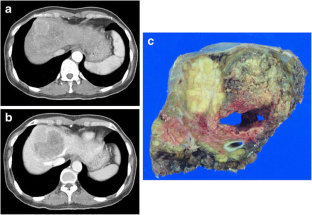

Fig. 1